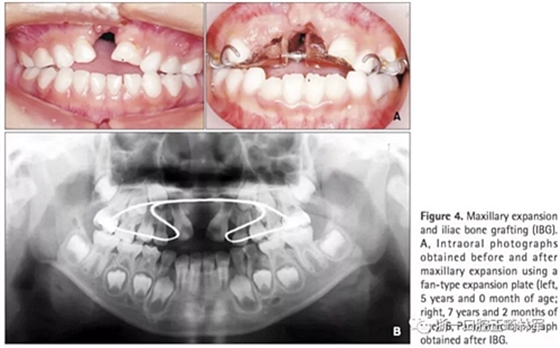

第一階段(圖4及表2)

上頜牙弓使用fan-type擴(kuò)弓器(慢擴(kuò),0.25mm/周)。7歲7月時行IBG,隨后上頜恒側(cè)切牙與移植區(qū)萌出。